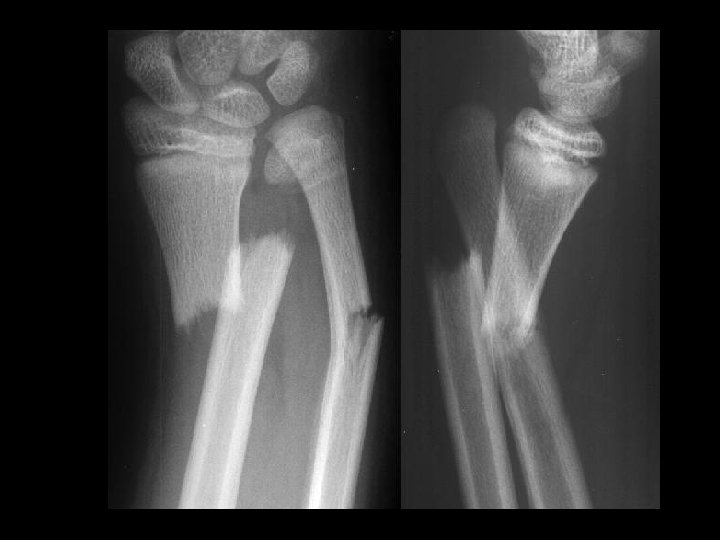

Galeazzi fracture-dislocation • Findings: – Angulated distal radius and ulna fractures – Distal ulnar dislocation • ddx: – NONE! – This is an Aunt Minnie!

Monteggia fracturedislocation • Findings: – Overlapping, angulated fracture of the proximal ulna – radial head dislocation • ddx: – NONE! – This is an Aunt Minnie!